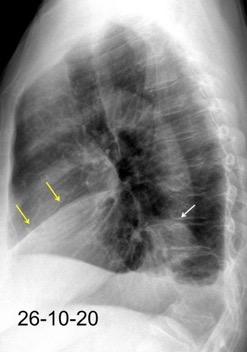

Tromboembolismo pulmonar.

Frecuencia del derrame:

Rx: 32%. TC: 47%

Unilateral. 85%

< 1/3 del hemitórax: 90%

Todos exudados

58% con eritrocitos

21% tabicación lo que causa demora en el diagnóstico

TEP. Empiema pleural. Atelectasia redonda

Porcel JM et al. Analysis of pleural effusions in acute pulmonary embolism: radiological and pleural fluid data from 230 patients. Respirology 2007/ Iguchi T et al. Desquamation of the subpleural lung parenchyma caused by empyema after pulmonary embolism: A case report. Respirol Case Rep. 2022 .